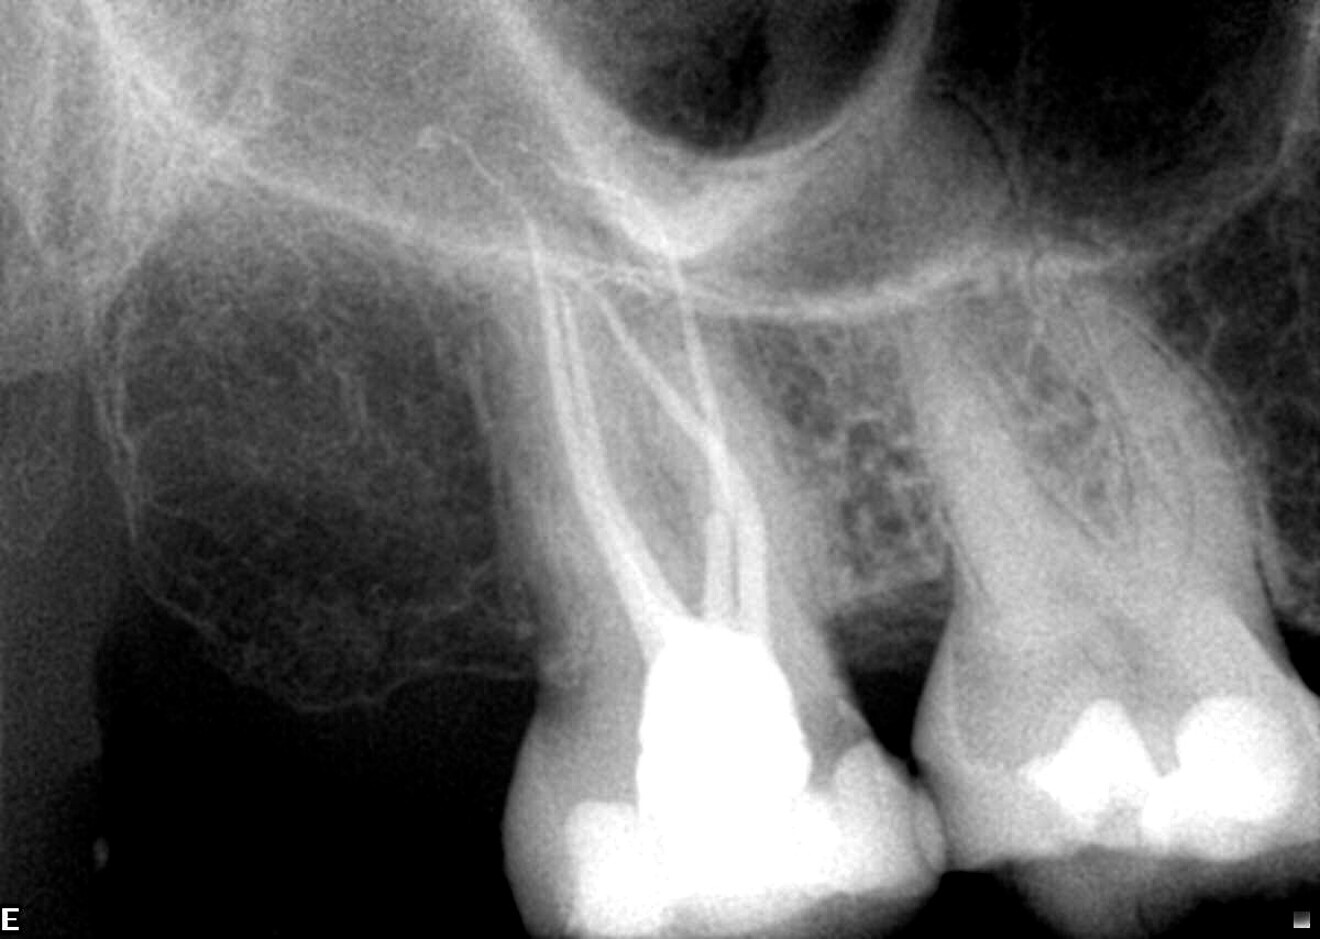

Fig. 1: The exceptionally sharp cutting edge of a ZenFlex CM file. (All images: Dr Philippe Sleiman)

Another advantage of the new procedure used in the creation of ZenFlex files lies in the development of an exceptionally sharp cutting edge (Fig. 1). As it is responsible for the actual cutting of dentine and therefore the shaping of the canal, the cutting edge is the essential working component of any file. This innovation brings multiple benefits: improved rotational speed, better preservation of the original anatomy, reduced working time within the canal, enhanced safety—and many more.